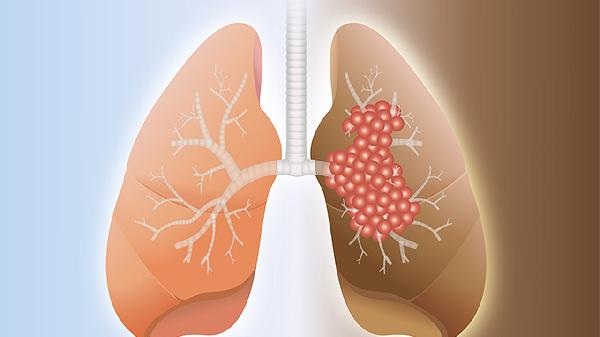

肺癌胸痛多为持续性钝痛,肿瘤侵犯胸膜或胸壁时加重,常伴咳嗽、痰中带血、消瘦。中央型肺癌可能压迫气管导致呼吸困难,周围型肺癌早期可无症状。诊断依赖胸部CT、支气管镜及病理活检,治疗包括手术切除、放疗、靶向药物如吉非替尼片等。早期发现预后较好,故高危人群应定期筛查。